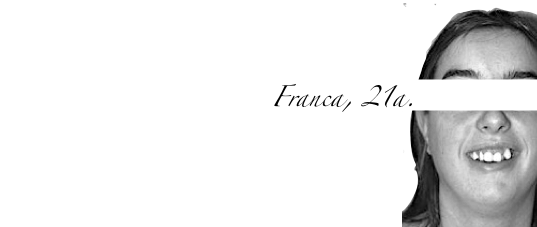

Nome

Franca

Età

21

Motivo dell’intervento

Inestetismo del sorriso